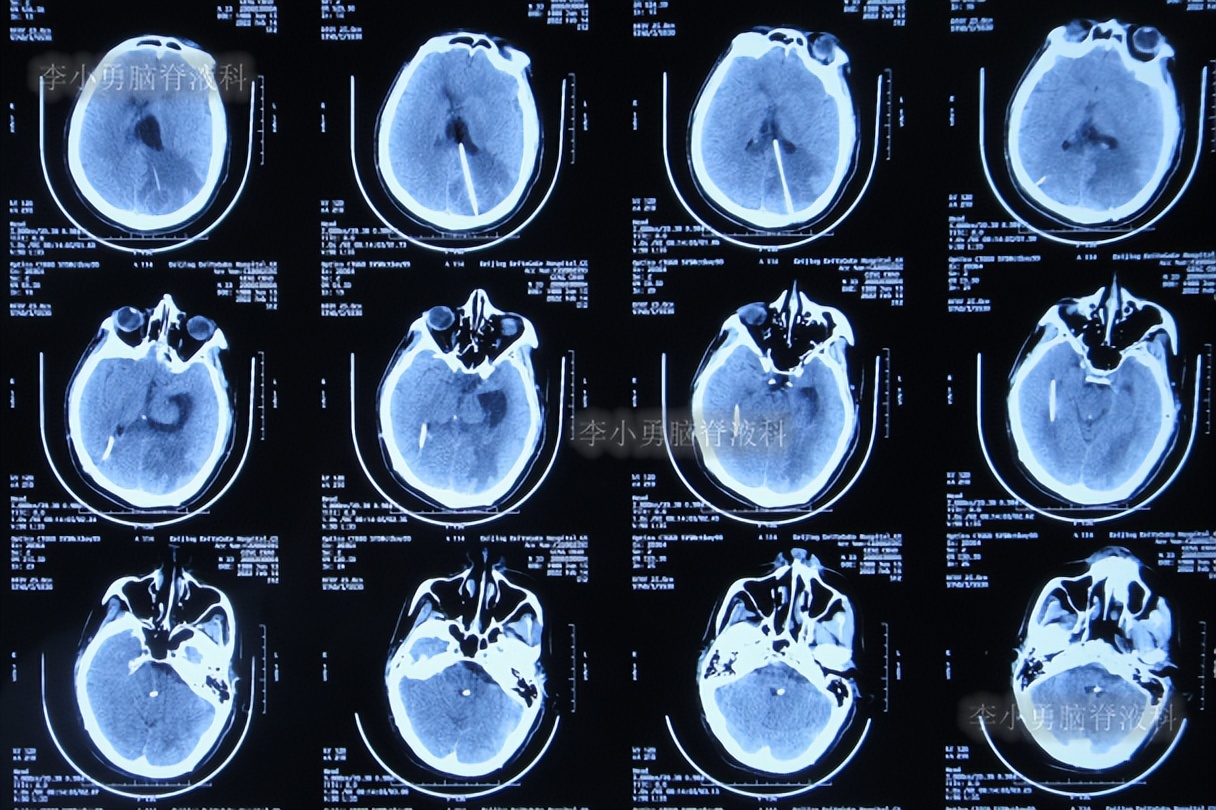

2022年11月15日(李小勇脑脊液科治疗151天)出院,出院时:意识正常,言语交流基本正常,自己走路差点(图-60);头颅CT示未见异常(图-61)。

图-60:2022年11月15日

图-61:出院时头颅CT